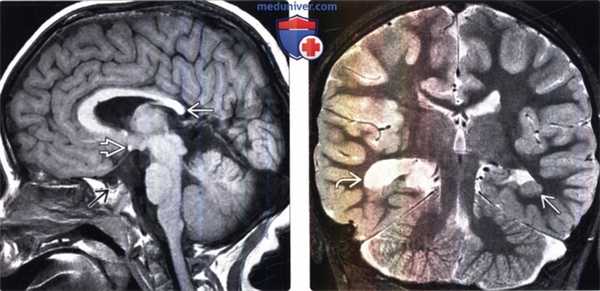

(Слева) МРТ, Т1-ВИ, сагиттальный срез: малые размеры гипофиза и отсутствие его воронки. Гиперинтенсивная эктопированная задняя доля гипофиза расположена на срединном возвышении. Мозолистое тело также дисморфично, валик которого имеет характерные малые размеры.

(Справа) МРТ, Т2-ВИ, корональный срез: у этого же пациента также определяются перивентрикулярная узловая гетеротопия серого вещества слева и дисплазия серого вещества нижних отделов височной доли. Киста хориоидальной щели справа, вероятно, не связана с основной патологией.

(Слева) MPT, Т1 -ВИ, сагиттальный срез: у пациента с септо-оптической дисплазией визуализируется яркая эктопированная задняя доля гипофиза . Обра тите внимание на небольшой зрительный перекрест и низкое расположение сводов головного мозга .

(Справа) МРТ, Т1-ВИ, сагиттальный срез: у пациента с удвоением гипофиза визуализируются утолщение дна турецкого седла и слияние серого бугра с сосцевидными телами (тубероммаммиллярное слияние). Обратите внимание на отсутствие по срединной линии турецкого седла и воронки гипофиза.